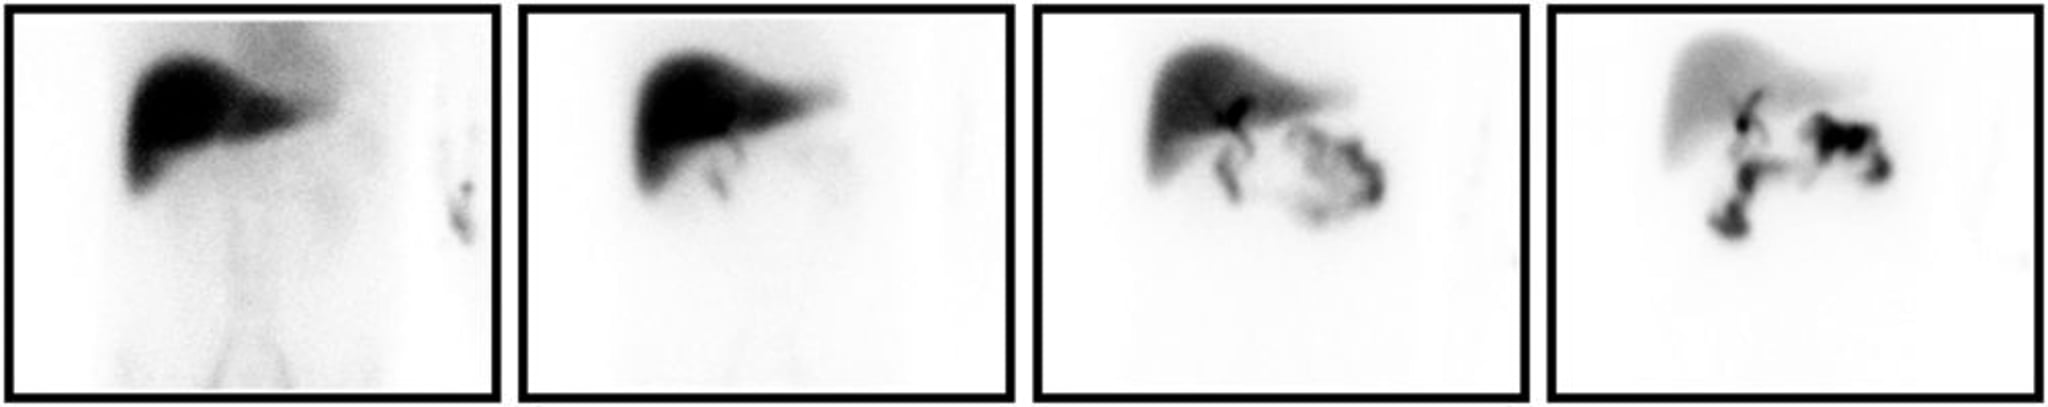

胆嚢炎と一致するHIDA scan画像。左から右に向かって,トレーサーを注射してから5分後,15分後,30分後,60分後の画像である。遅い時点の画像でも,胆嚢の充満が認められない。